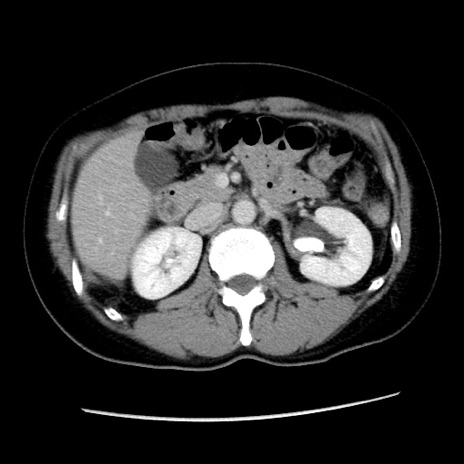

冠状断像

【症例】 50歳代女性

【主訴】 腹痛

【現病歴】前日生レバーを食べた。今朝に排便あり。 昼前に突然発症の腹痛を生じ、当院救急外来を受診した。

【既往歴】 子宮筋腫にてで子宮全摘後

【身体所見】 意識清明、腹部:平坦、軟、下腹部やや左を中心に圧痛・反跳痛あり、筋性防御あり

【データ】WBC 7800、CRP 0.07